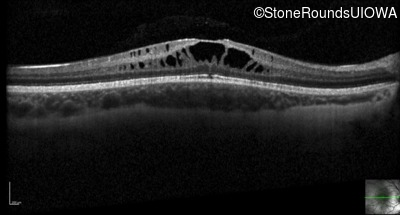

Optical Coherence Tomography - Left - 20/40

Exemplar / OCT Stack